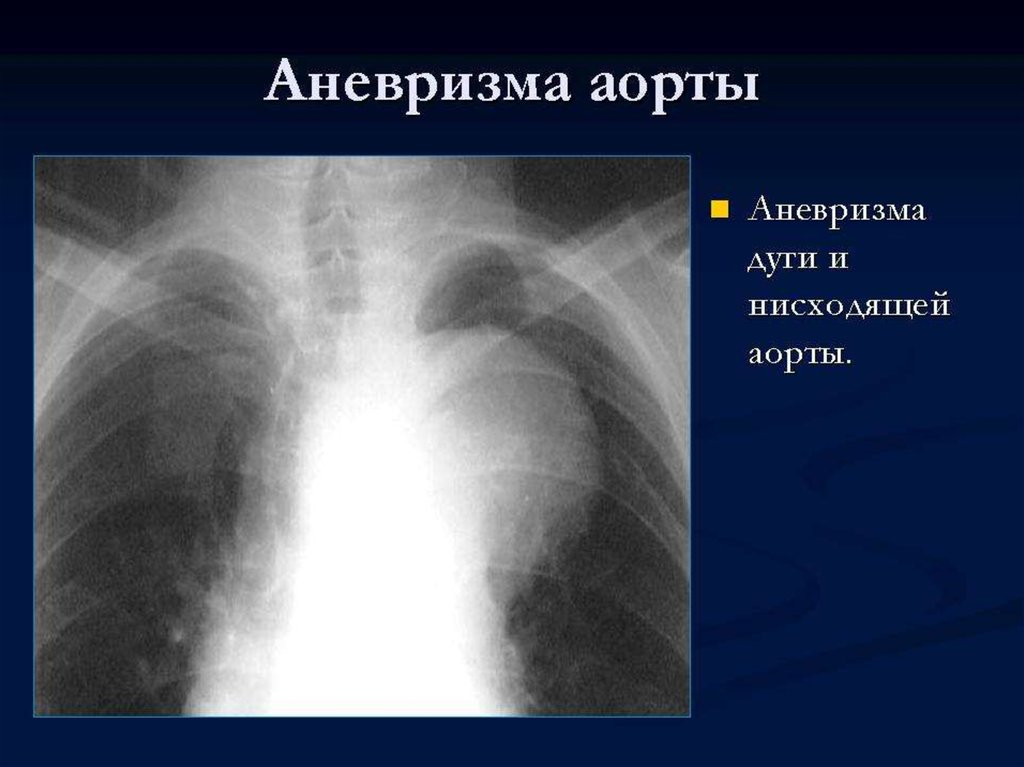

Рентгенограмма аорты

Рентгенограмма аорты 114 фотографий